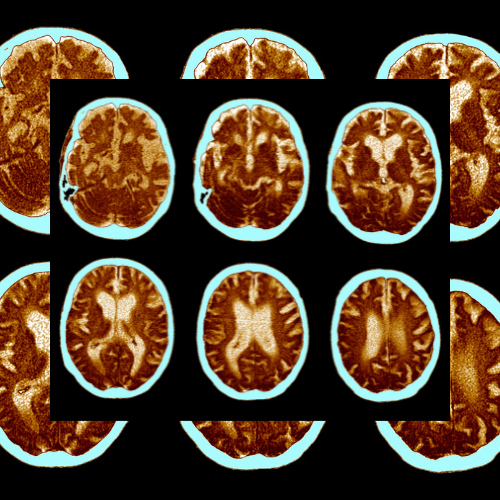

치매는 단순히 기억력이 나빠지는 것을 말하지 않습니다. 치매는 여러 가지 이유로 뇌의 기능이 떨어지는 것을 말합니다. 이로 인해 기억력, 생각하는 능력, 문제를 해결하는 능력, 말을 하는 능력 등이 떨어져서 일상 생활에 큰 불편을 겪게 됩니다. 치매는 다양한 원인에 의해 생길 수 있습니다.

알츠하이머는 치매의 가장 흔한 원인 중 하나로, 뇌의 특정 부분이 손상되어 생기는 병입니다. 뇌 속에 이상한 단백질이 쌓이면서 뇌세포가 죽어갑니다. 처음에는 기억력이 조금씩 나빠지기 시작하지만, 점점 더 심해지면서 일상 생활을 하기가 어려워집니다.

많은 사람들이 치매와 알츠하이머를 헷갈려 하지만, 두 가지는 다른 것입니다. 치매는 여러 가지 원인으로 뇌의 기능이 떨어지는 상태를 말하고, 알츠하이머는 그 중 하나의 원인으로 특정한 뇌 손상으로 생기는 병입니다.